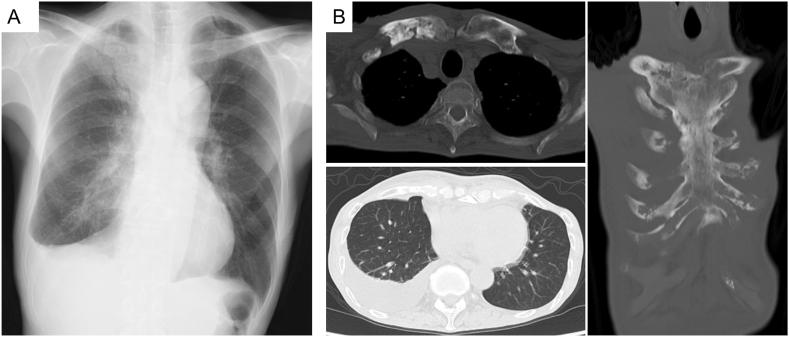

A 79-year-old man presented with fatigue and right shoulder pain. Computed tomography revealed right pleural effusion and osteosclerosis of the sternoclavicular joint. There were no signs of malignancy or infection in the pleural fluid studies. His bone scintigraphy exhibited the "bull's head sign." Despite the absence of skin lesions, he was diagnosed with synovitis-acne-pustulosis-hyperostosis-osteitis (SAPHO) syndrome. Remission was achieved after treatment with non-steroidal anti-inflammatory drugs and oral prednisolone. SAPHO syndrome causes pleural effusion, even in patients without skin lesions. Bone scintigraphy should be considered in the workup for patients with unexplained pleural effusion.

一名79岁男性因疲劳和右肩疼痛就诊。计算机断层扫描显示右侧胸腔积液和胸锁关节骨硬化。胸腔积液检查未发现恶性肿瘤或感染迹象。他的骨闪烁显像显示出“牛头征”。尽管没有皮肤病变,但他被诊断为滑膜炎-痤疮-脓疱病-骨肥厚-骨炎(SAPHO)综合征。使用非甾体抗炎药和口服泼尼松龙治疗后病情缓解。SAPHO综合征即使在没有皮肤病变的患者中也可导致胸腔积液。对于不明原因胸腔积液的患者,在检查过程中应考虑进行骨闪烁显像。